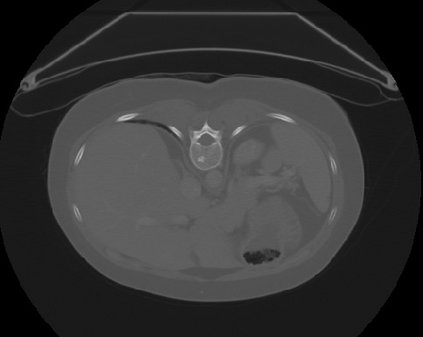

Transformers, the default model of choices in natural language processing, have drawn scant attention from the medical imaging community. Given the ability to exploit long-term dependencies, transformers are promising to help atypical convolutional neural networks (convnets) to overcome its inherent shortcomings of spatial inductive bias. However, most of recently proposed transformer-based segmentation approaches simply treated transformers as assisted modules to help encode global context into convolutional representations without investigating how to optimally combine self-attention (i.e., the core of transformers) with convolution. To address this issue, in this paper, we introduce nnFormer (i.e., Not-aNother transFormer), a powerful segmentation model with an interleaved architecture based on empirical combination of self-attention and convolution. In practice, nnFormer learns volumetric representations from 3D local volumes. Compared to the naive voxel-level self-attention implementation, such volume-based operations help to reduce the computational complexity by approximate 98% and 99.5% on Synapse and ACDC datasets, respectively. In comparison to prior-art network configurations, nnFormer achieves tremendous improvements over previous transformer-based methods on two commonly used datasets Synapse and ACDC. For instance, nnFormer outperforms Swin-UNet by over 7 percents on Synapse. Even when compared to nnUNet, currently the best performing fully-convolutional medical segmentation network, nnFormer still provides slightly better performance on Synapse and ACDC.